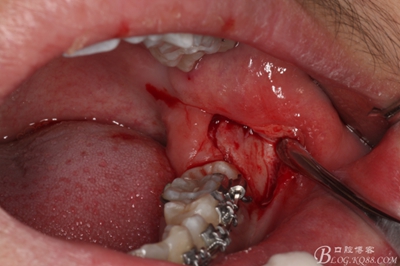

圖7.翻開粘骨膜瓣。

圖8。暴露出頰側(cè)骨壁,38完全位于骨內(nèi)